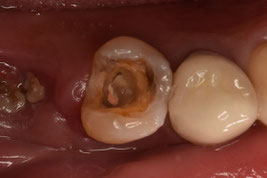

広範囲に軟化象牙質を認めましたが、歯肉縁上に十分な健全歯質を保存できたため、根管治療を施術しました。前医での複数枚のレントゲン写真があったため、そちらを参考に処置を進めました。

1回法で根管治療を終わらせてデンタルを撮影したところ、目を疑う光景がありました。

「6番の近心根がほぼそのまま残根しているぞ!…どうしよう」

根尖だけ若干残るのなら分かります。しかし、近心根がまるごと残っているのです。

これが日本よりも医療技術が進んでいる治療なのですか。

呆れて言葉が出ません。

患者さんに残根について説明し、限られたアポイントの中で、なんとか抜歯できました。